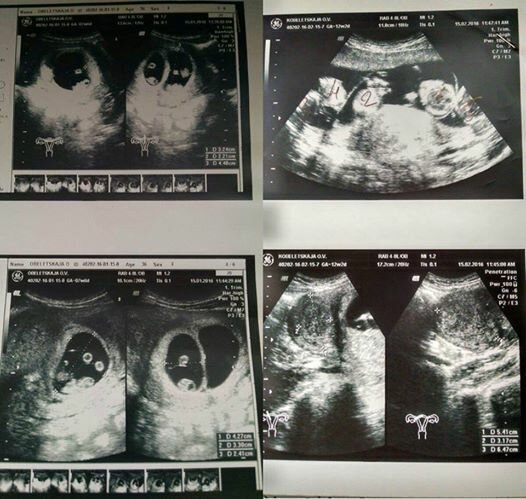

Na dalším ultrazvuku si všimla, že se doktor zamračil a opakoval vyšetření. Velmi se obávala, že se svým dětem něco děje.

Nečekala, že jí doktor oznámí, že nemá v sobě dvojčata, ale ... pět dětí! A co víc, lékař řekl, že v tak ranné fázi je obtížné si být absolutně jistý, a může se ukázat, že existuje šest plodů! K tomu dochází jednou za 55 milionů těhotenství. Oksana tomu nemohla uvěřit.